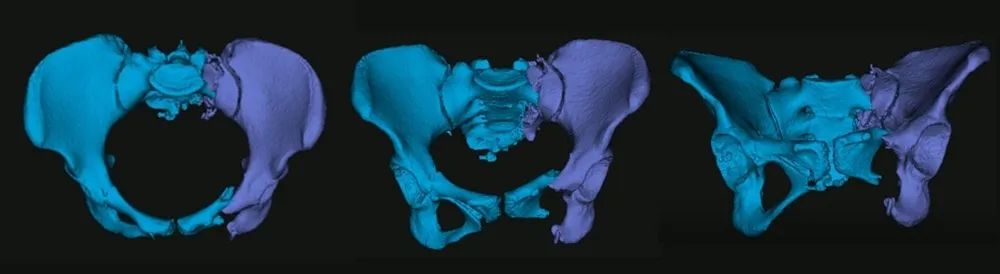

图二:患者术前影像资料

该患者为年轻女性,伤势严重且伤后等待救治时间较长(伤后13天接受手术),除了骨盆骨折之外,还合并胸腰椎多发骨折并不全瘫,肾、脾挫伤。若采用传统术式,损伤较大,且需要分期治疗骨盆骨折及腰椎骨折,同时还有继发脏器出血的风险。副院长孙涛、东院创伤一科主任洪焕玉及其团队反复讨论后决定实施创新术式,采用目前全球最先进的“智能化骨科手术机器人全流程辅助骨盆骨折闭合复位内固定手术”治疗方式。

术前,手术团队进行了周密的准备,基于患者术前影像,借助基于AI与大数据的自动手术规划,将患者健侧肢体进行镜像配准,通过精细化自动分割与重建,实现个性化、定量化的复位规划。

图三:自动分割与重建

图四:人工智能复位规划